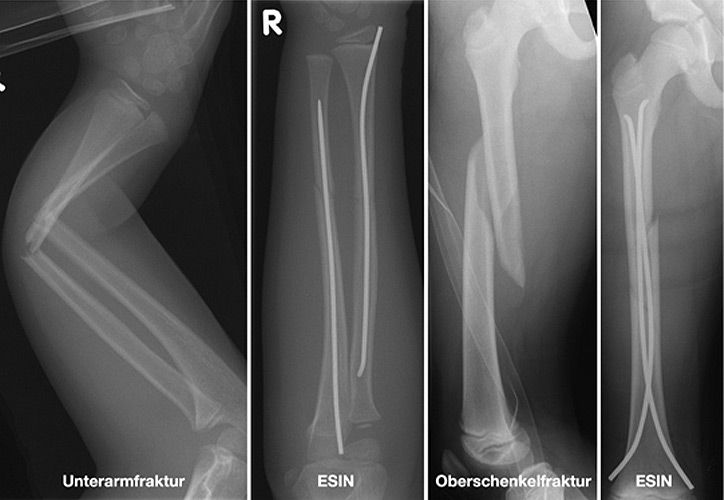

Elastisch stabile intramedulläre Nagelung

Einige Frakturen müssen auf Grund ihrer Achsabweichung operiert werden. In einer Narkose wird die Fraktur eingerichtet und ggf. mit Metall stabilisiert. Dazu stehen eine Reihe von Methoden (Osteosynthesen) zur Verfügung, die speziell für Kinder entwickelt wurden, um Wachstumsfugen zu schonen und nicht zu verletzen: Die ESIN (elastisch stabile intramedulläre Nagelung) hat sich als minimal invasives Standardverfahren zur Stabilisierung von Schaftfrakturen der großen Röhrenknochen (Unterarm, Oberarm, Unterschenkel, Oberschenkel) etabliert. Die Implantate können über winzige Schnitte eingebracht werden, eine gipsfreie Nachbehandlung ist ein weiterer entscheidender Vorteil.

Kirschner-Draht-Osteosynthese